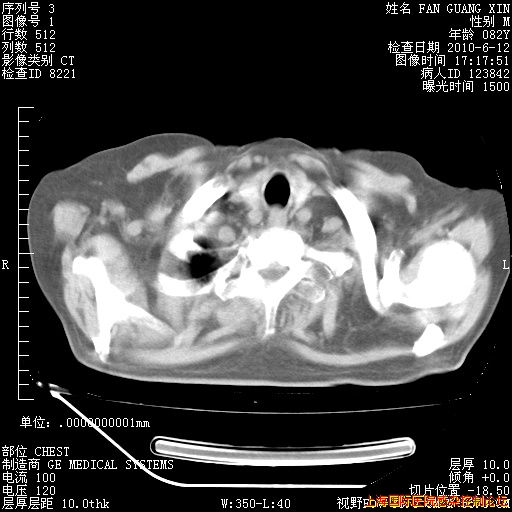

6月12日纵膈窗

整整相隔30天的肺部CT好像有所好转啊。甲强龙减量第3天,需要观察体温。